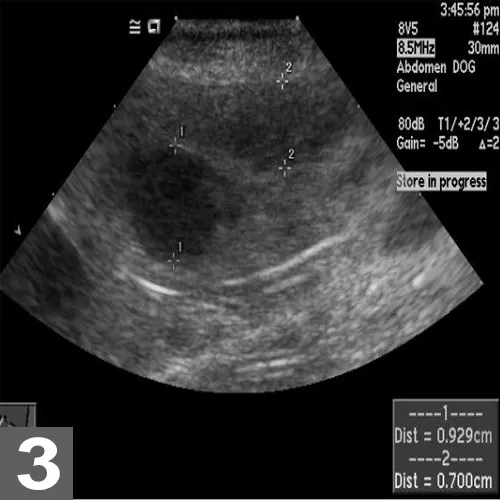

Abdominal Ultrasonography

When MCTs are present caudally, abdominal ultrasonography is used to assess the spleen and liver. Fine-needle aspiration of these organs may be useful, especially when a lesion is visible.

Abdominal ultrasonography is also critical for assessing sublumbar lymph nodes when an MCT is present on the caudal aspect of a patient.

A cytologist needs to assess whether the appearance, number, and clustering of mast cells suggest metastasis.

Ultrasound image of MCTs in the spleen of a dog with systemic mast cell disease. The patient’s primary tumor was located on the muzzle and controlled for 1 year until systemic progression occurred.